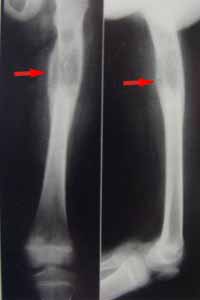

腓骨骨腫瘤X線表現一、放射學檢查

X線檢查對明確骨腫瘤性質、種類、範圍及決定治療方針都能提供有價值的資料,是骨腫瘤重要的檢查方法。然而X線片僅是骨腫瘤的投影,骨腫瘤的X線表現不恆定,需密切結合臨床表現和病理檢查,才能作出準確診斷。

良性骨腫瘤形態規則,與周圍正常骨組織界限清楚,以硬化邊為界,骨皮質因膨脹而變薄,但仍保持完整,無骨膜反應,惡性腫瘤的影像不規則,邊緣模糊不清,溶骨現象較明顯,骨質破壞,變薄,斷裂,缺失,原發性惡性腫瘤常出現骨膜反應,其形狀可呈陽光放射狀,蔥皮樣及Codman三角。

X線片可為醫生提供有關腫瘤發病過程四個信息:

1、骨腫瘤的位置 如腫瘤可位於骨骺,也可位於乾骨骺端,可位於長骨,也可位於扁平骨;青少年骨骺發生的腫瘤應首先考慮軟骨母細胞瘤,而成年人上述骨骺部的腫瘤應考慮為骨巨細胞瘤。

2、腫瘤對宿主骨的影響 腫瘤與宿主骨間邊界有無浸潤性是確定病變性質的首要因素,邊界清楚者表明腫瘤生長緩慢且浸潤性弱。反之,邊界模糊者則表明腫瘤浸潤性強。

3、宿主對腫瘤的反應 宿主總是力圖消滅腫瘤,將其包裹,形成纖維組織包膜,生長快速的腫瘤可浸潤和破壞這種反應性骨包膜,而僅在腫瘤的一端或兩端能見到這種包膜的殘餘,通常表現為Codman三角。

4、腫瘤組織的密度 骨組織顯像中如有任何密度變化,均可懷疑該組織有病變,有些腫瘤為溶骨性病變,如骨巨細胞瘤,而有些為成骨性病變,成骨不規則或為雪花狀,如骨肉瘤、軟骨肉瘤。